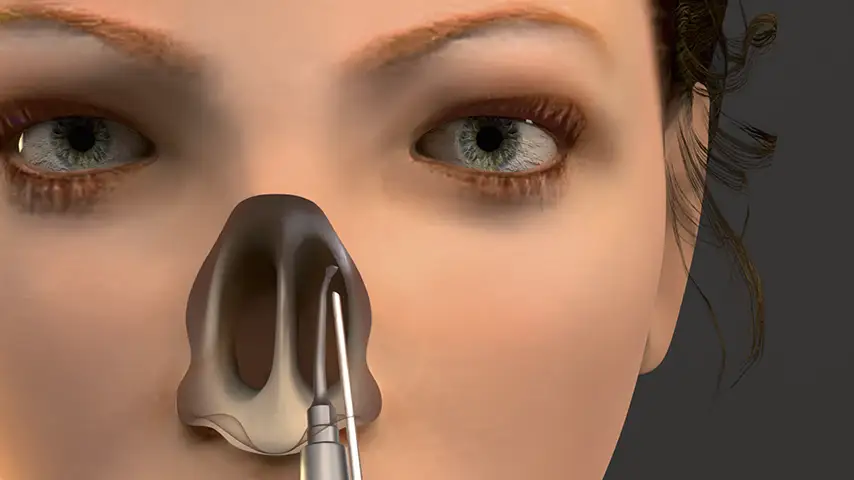

Clinical Applications of PIEZOSURGERY® technology

in Rhinoplasty

Hump takedown and dorsum modeling

Lateral osteotomy of nasal bone

Transverse osteotomy of nasal bone

Drilling of septum for suture fixation

Details

The finest and angled insert for insertion in limited space;

ideal for perforating nasal bones as well as ethmoid lamina splints.

Advantages over traditional tools

Reduced risk of damaging anatomically complex regions

Greater intraoperative control and bone management

Micrometric cut for minimal bone loss

Reduced heat generation to avoid bone necrosis